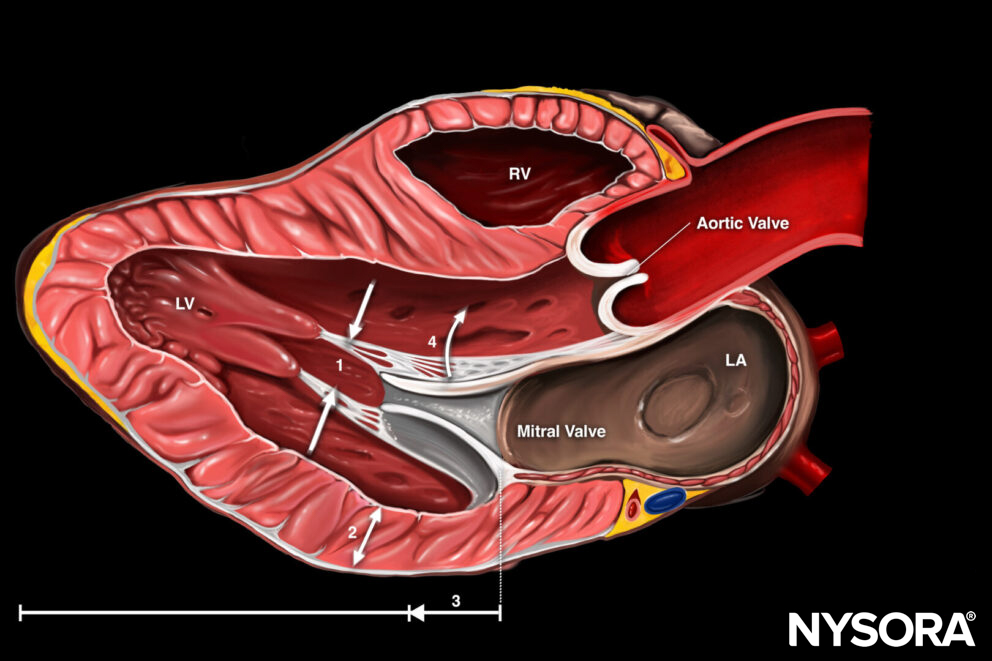

Peripheral vascular access in adults can be obtained on the upper and lower extremities.

Anatomy of the veins of the upper limb and foot.